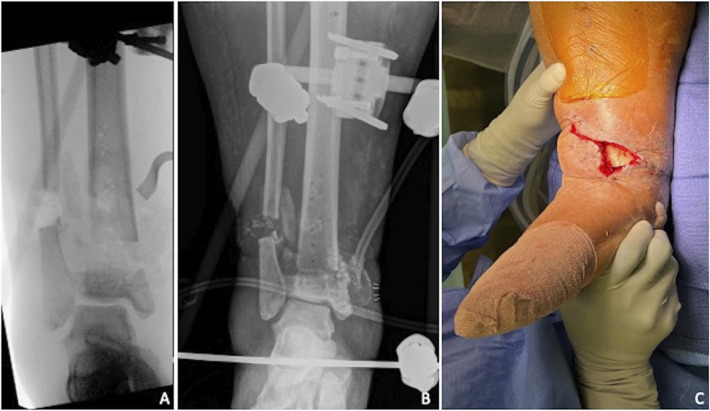

Case: A 42-year-old African-American woman sustained a type IIIA open pilon fracture requiring open reduction internal fixation complicated by wound dehiscence. Acute shortening for primary wound closure was performed followed by relengthening in a circular frame. Owing to the patient's intolerance to the circular frame, pre-existing osseous deformity, large body habitus, and soft tissue compromise, conversion to intramedullary stabilization with standard nailing was deemed exceedingly difficult. We describe the use of a photodynamic bone stabilization system allowing for percutaneous entry and implant flexibility for the purpose of early circular frame removal.

Conclusion: This case demonstrates successful protection of immature regenerate using a photodynamic bone stabilization system, offering another tool to minimize time spent in a circular frame.